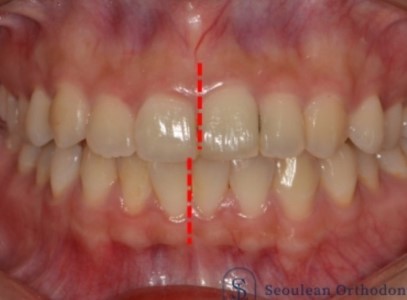

분당교정치과 / 치아 중심선이 어긋나서 고민이라면? – 실제 치료 사례